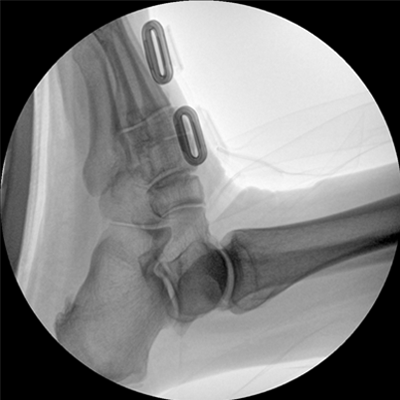

智能化控制系統(tǒng), 讓手術(shù)高效暢捷

四維電動(dòng)運(yùn)動(dòng)控制,平滑定位,使得復(fù)雜角度快速實(shí)現(xiàn)。

專(zhuān)業(yè)的圖像處理系統(tǒng),為您提供高分辨率、高灰階圖像。